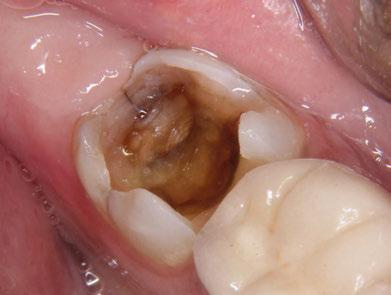

Exploración Intraoral

Presenta un estado oral deficitario. Parcialmente edéntula, con colapso de mordida, migración dental patológica, restauraciones de resina antiguas fisuradas y filtradas, transparencia y exposición de cámara pulpar secundaria a desgastes con pérdida de estructura e integridad de tejido dental importante (Figuras 1 a 4). Portadora a tiempo parcial de prótesis removibles desadaptadas de más de 10 años de antigüedad, refiriendo incapacidad de adaptación a este tipo de prótesis.

Figura 3. Visión intraoral oclusal mandibular. Figura 4. Visión intraoral frontal. Figura 1. Visión intraoral oclusal maxilar. Figura 2. Visión lateral izquierda intraoral. Figura 7. Escaneado intraoral maxilar con Dexis IS3700. Figura 8. Escaneado intraoral mandibular con Dexis IS3700. Figura 5. Visión extraoral lateral sonrisa.